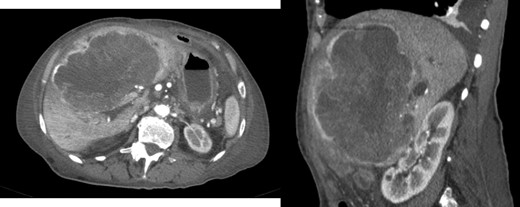

At 16 months, follow-up, local recurrence was identified on CT scan, showing an expansive heterogeneous lesion, below the stomach, with 7.4 cm of maximum diameter, showing no cleavage plan with the stomach (Fig. 4).

AP-CT – expansive heterogeneous lesion, with 7.4 cm, showing no cleavage plan with the stomach.

After 11 months of follow-up, the patient was admitted to the emergency room due to asthenia, nausea, vomiting and jaundice. CT scan reveal hepatic mass with 15.2 × 13.5 × 8.8 cm (Fig. 5) causing obstructive jaundice by compression of hepatic hilum.